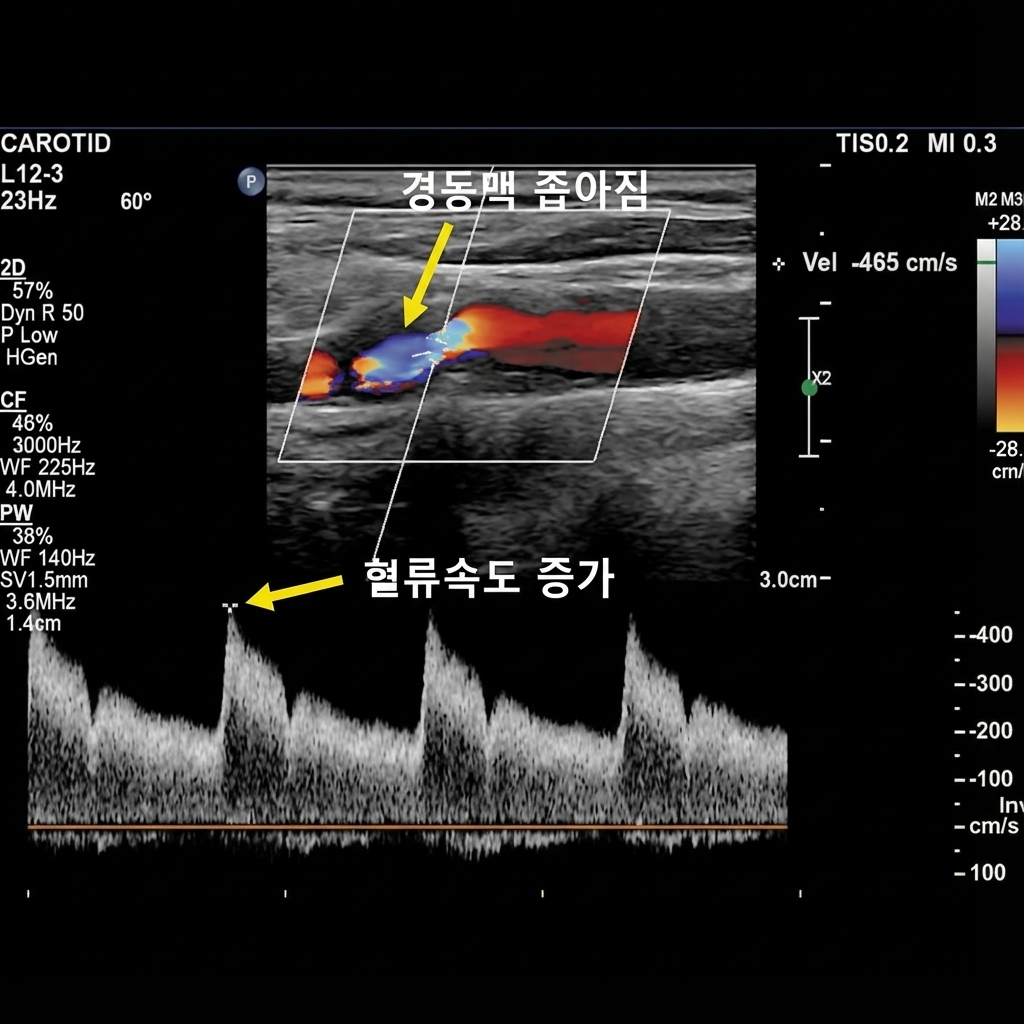

협착 정도 (Stenosis)

경동맥이 플라크로 인해 얼마나 좁아졌는지를 백분율(%)로 표시합니다. 50% 미만은 경도 협착, 50~69%는 중등도 협착, 70% 이상은 고도 협착으로 분류됩니다. 고도 협착은 뇌졸중 위험이 높아 약물 치료뿐만 아니라 수술(경동맥 내막 절제술) 또는 스텐트 시술이 필요할 수 있습니다.

혈류 속도 (Flow Velocity)

도플러 초음파로 측정한 혈류 속도가 정상보다 빠르면 협착이 의심됩니다. 혈관이 좁아지면 그 부분을 지나는 혈류가 빨라지므로, 협착 정도를 간접적으로 평가할 수 있습니다. 혈류 속도와 영상 소견을 함께 판단하여 협착 정도를 정확히 평가합니다.